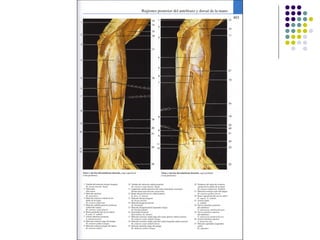

La extremidad superior humana incluye el hombro, el brazo, el codo, la muñeca y la mano. Está diseñada para una variedad de funciones motoras finas como agarrar objetos y realizar tareas manuales complejas. La coordinación precisa de los músculos y los huesos de la extremidad superior es clave para su versatilidad funcional.